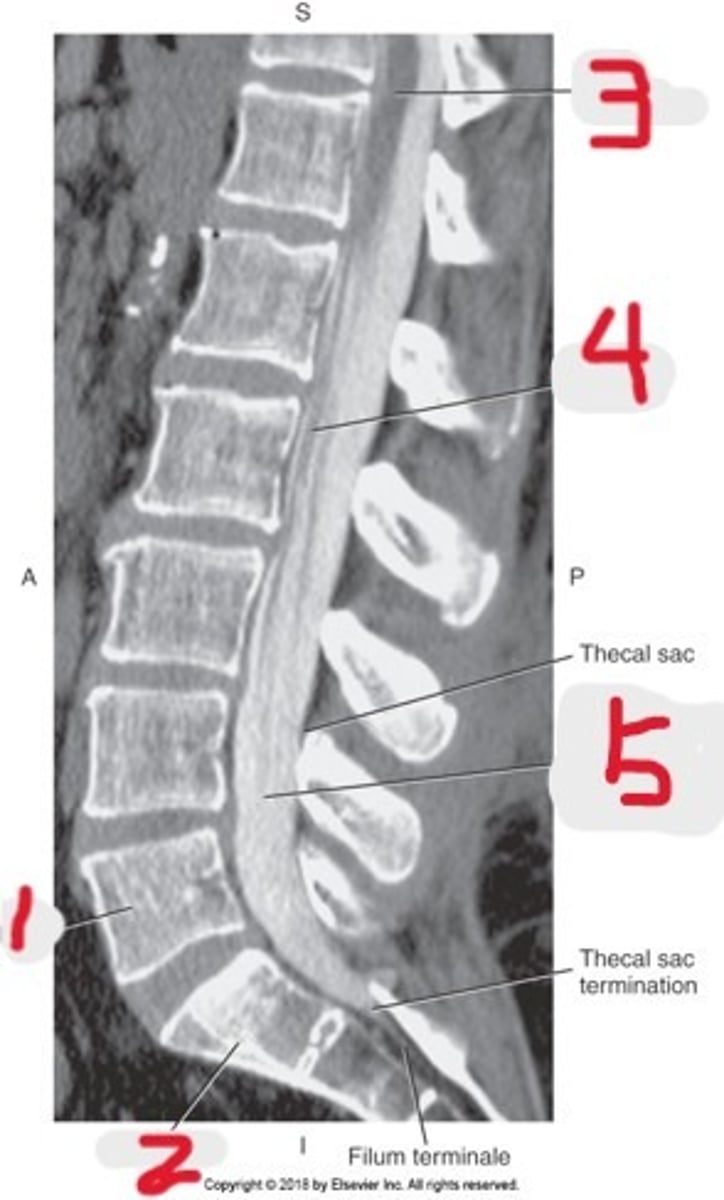

1) L5

2) Sacrum

3) Conus medullaris

4) Cauda equina

5) Subarachnoid space with contrast

Name all numbered structures